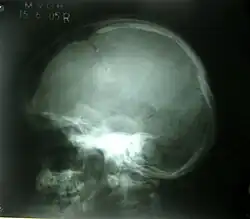

Диагностика ключично-черепного дизостоза основана на клинических симптомах и рентгенологических исследованиях, которые включают изображения черепа, грудной клетки, таза и рук. Главный рентгенологический симптом — дефекты ключиц. Обычно отсутствует наружный (акромиальный) конец ключицы, в то время как внутренний (грудинный) конец присутствует. Но иногда ключица состоит из двух фрагментов. Полное отсутствие ключицы встречается редко.